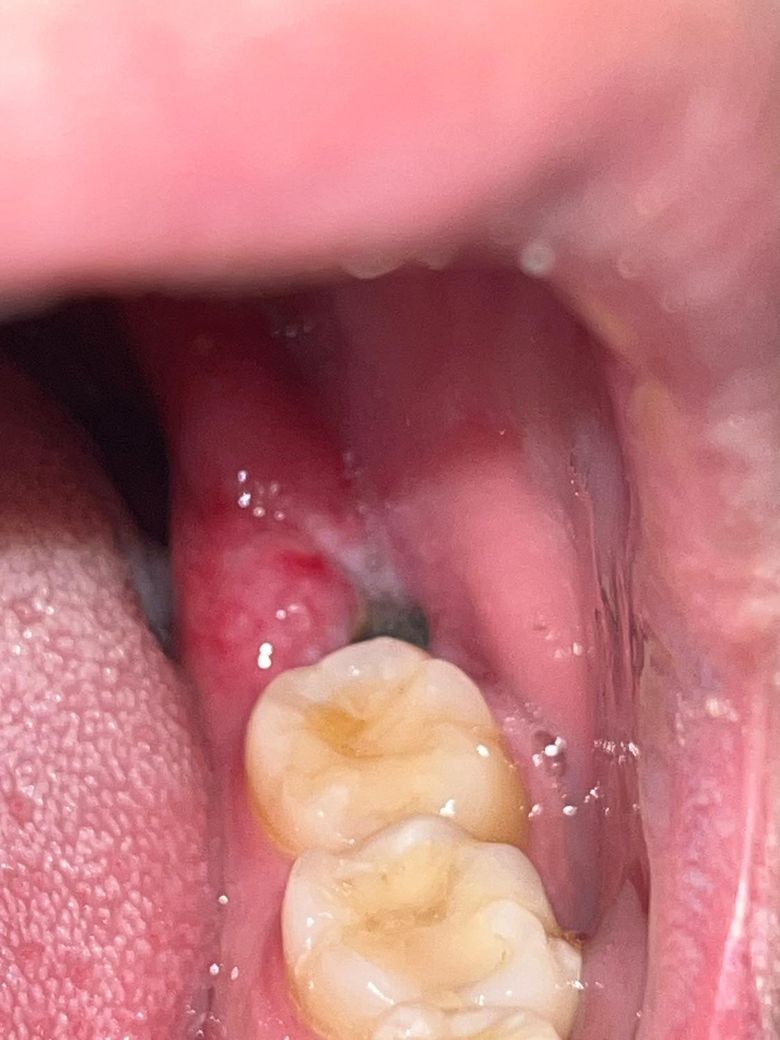

사랑니 발치 일주일 실밥 풀었는데 드라이소켓일까요?

안녕하세요 사랑니 발치하고 일주일되는 오늘 실밥을 풀고 왔습니다.

근데 선생님 말로는 상처가 덜아물었다고 하셔서

별걱정은 안했는데 워낙 사랑니 관련 드라이소켓 이런게 뜨다보니 걱정이 되서 질문 남깁니다.

1.혹시 드라이소켓일까요?

육안으로 봤을떄는 안에 하얀색깔 처럼 보이기는 합니다.

1. 드라이소켓은 아닙니다. 그랬다먼 발치 3일차정도부터 극심한 통증에 시달리셨을테고 지금은 잘 아물고 있는 것으로 보입니다.

드라이소켓의 양상은 아닙니다

발치하신지 일주일정도 지나셧다면 드라이소켓은 아닙니다. 잇몸이 차오르려면 최소 한달정도는 시간이 소요됩니다.